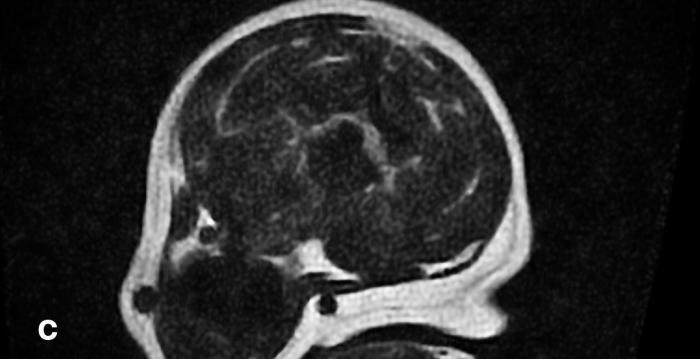

La descompresión consistió en el fresado controlado de los cuerpos vertebrales hasta exponer el canal espinal, retirándose el material discal extruido mediante instrumental microquirúrgico (Figura 3). Se realizó una exploración meticulosa para asegurar la remoción completa del material y se descartó la presencia de hemorragia venosa significativa. El cierre quirúrgico se llevó a cabo por planos.

Figura 3. Extracción de material discal extruido.